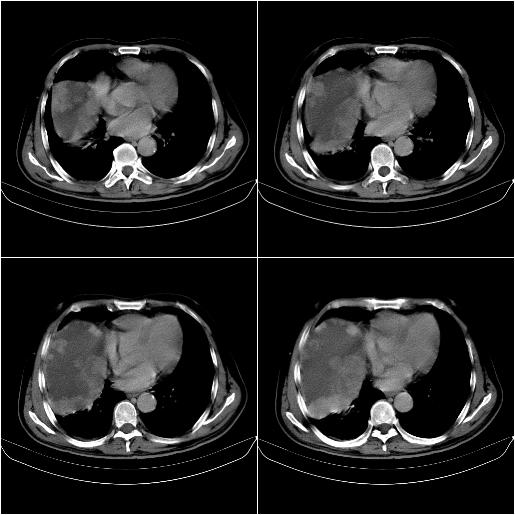

标题: CT21651:M,67Y,肝癌9月,介入术后3月。

m,67y,肝癌9月,介入术后3月。现腹胀、纳差、腹泻。

1)肝癌介入治疗术后碘油沉积不良。2)门静脉瘤栓形成,腹膜广泛性转移。3)肝硬化,脾大,腹水。4)慢性胆囊炎。